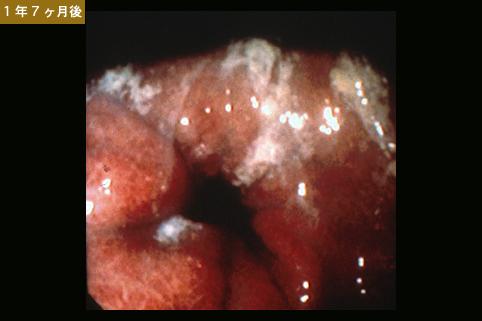

进行性胃癌4型(弥漫浸润型)

曾被诊断为典型的IIc型早期胃癌,但当时拒绝了手术,于1年零7个月后因进展期胃癌而施行了胃切除的病例。

恶性上皮性肿瘤/印戒细胞癌

4型(弥漫浸润型)/

s(a)